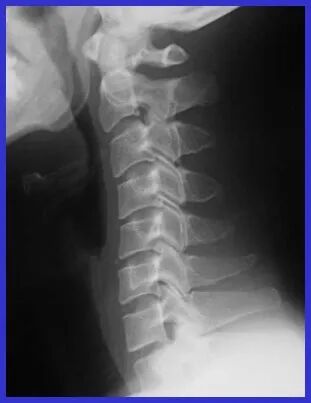

放射学检查

•颈椎生理弯曲消失或反向成角 •椎间隙狭窄,椎体退行性变 •椎间关节松动(动力学摄片) •椎管矢状径 <12~10mm

颈椎病X线片特征